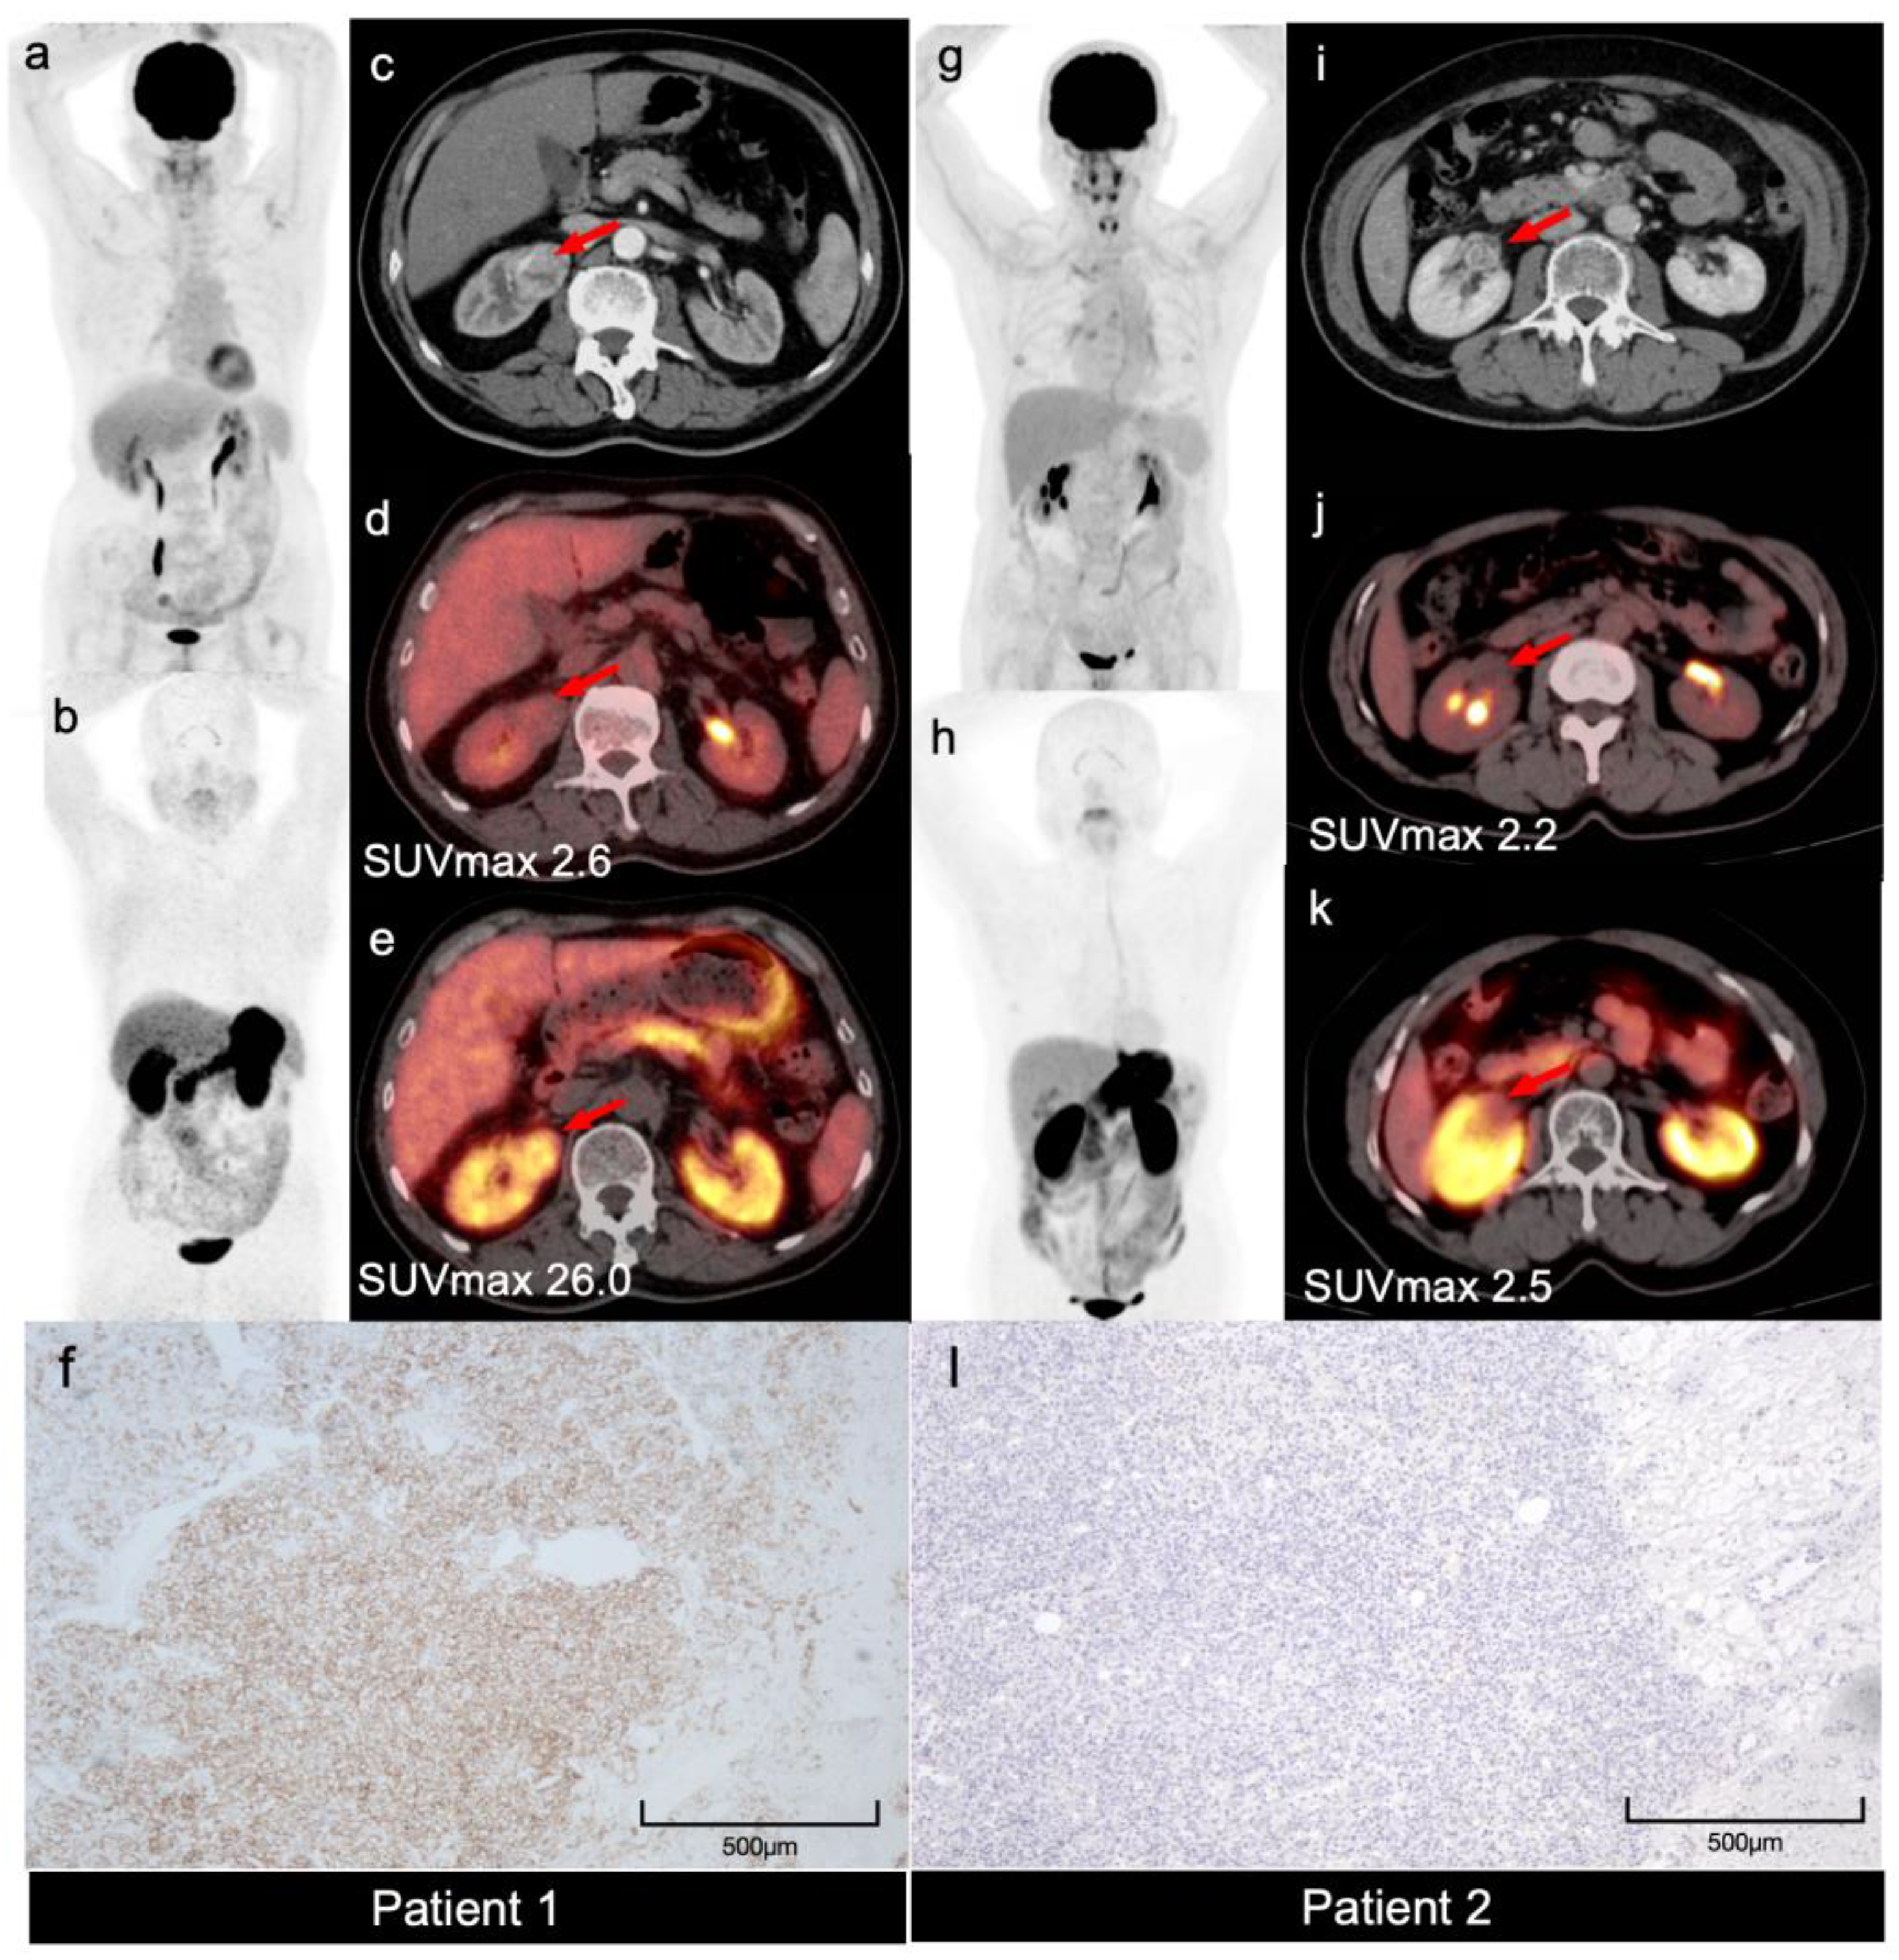

68Ga-NY104 PET/CT in the Differential Diagnosis of FDG-Negative Renal Masses: A Two-Case Illustration of Clear Cell Carcinoma Versus Renal Hemangioma